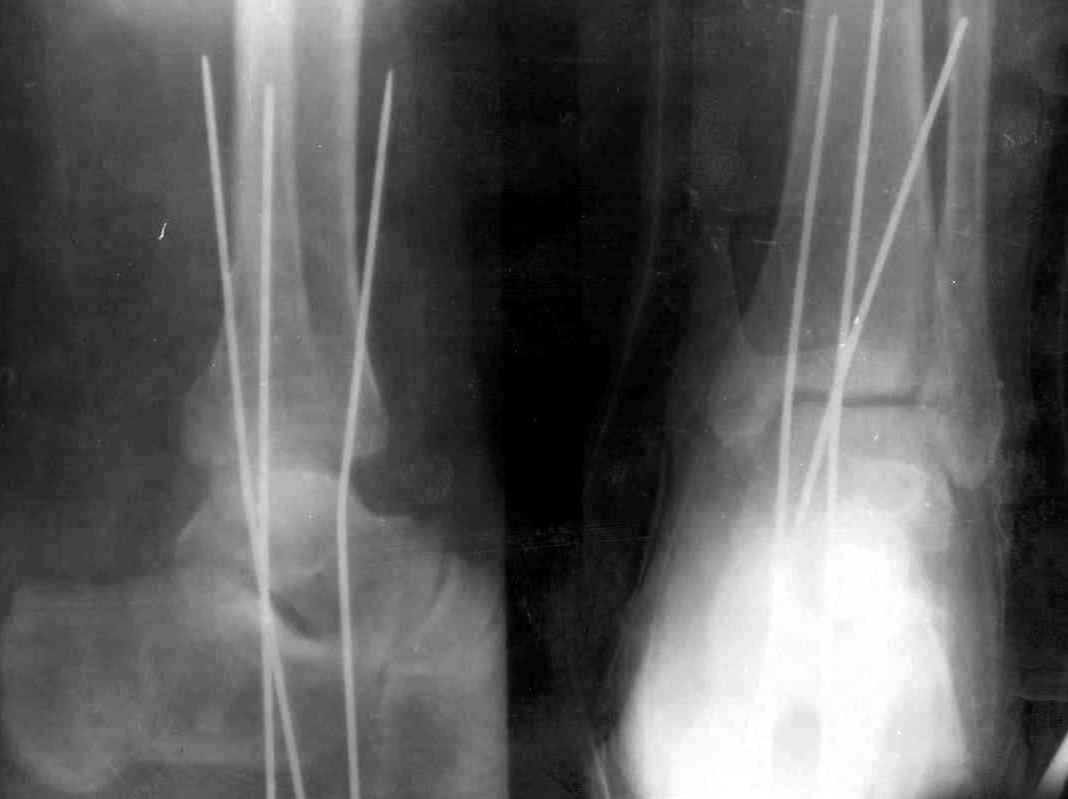

> трансартикулярная диафиксация спицами. Веду больную без иммобилизации.

Довольно рискованно (видел больного со сломанными спицами)

В течение длительного времени у нас принят этот способ фиксации, по показаниям конечно. Тактика такая: После репозиции и ТАФ стопы, гипсовая шина обязательно. Ч/з 7 дней Рентгенконтроль. Спицы удаляем через 1,5 мес, и затем продлеваем гипсовую иммобилизацию до 2-2,5 мес. Результатами я честно говоря доволен. Если спицы убрать раньше или вести совсем без них, то очень вероятно вторичное смещение. Удачи!